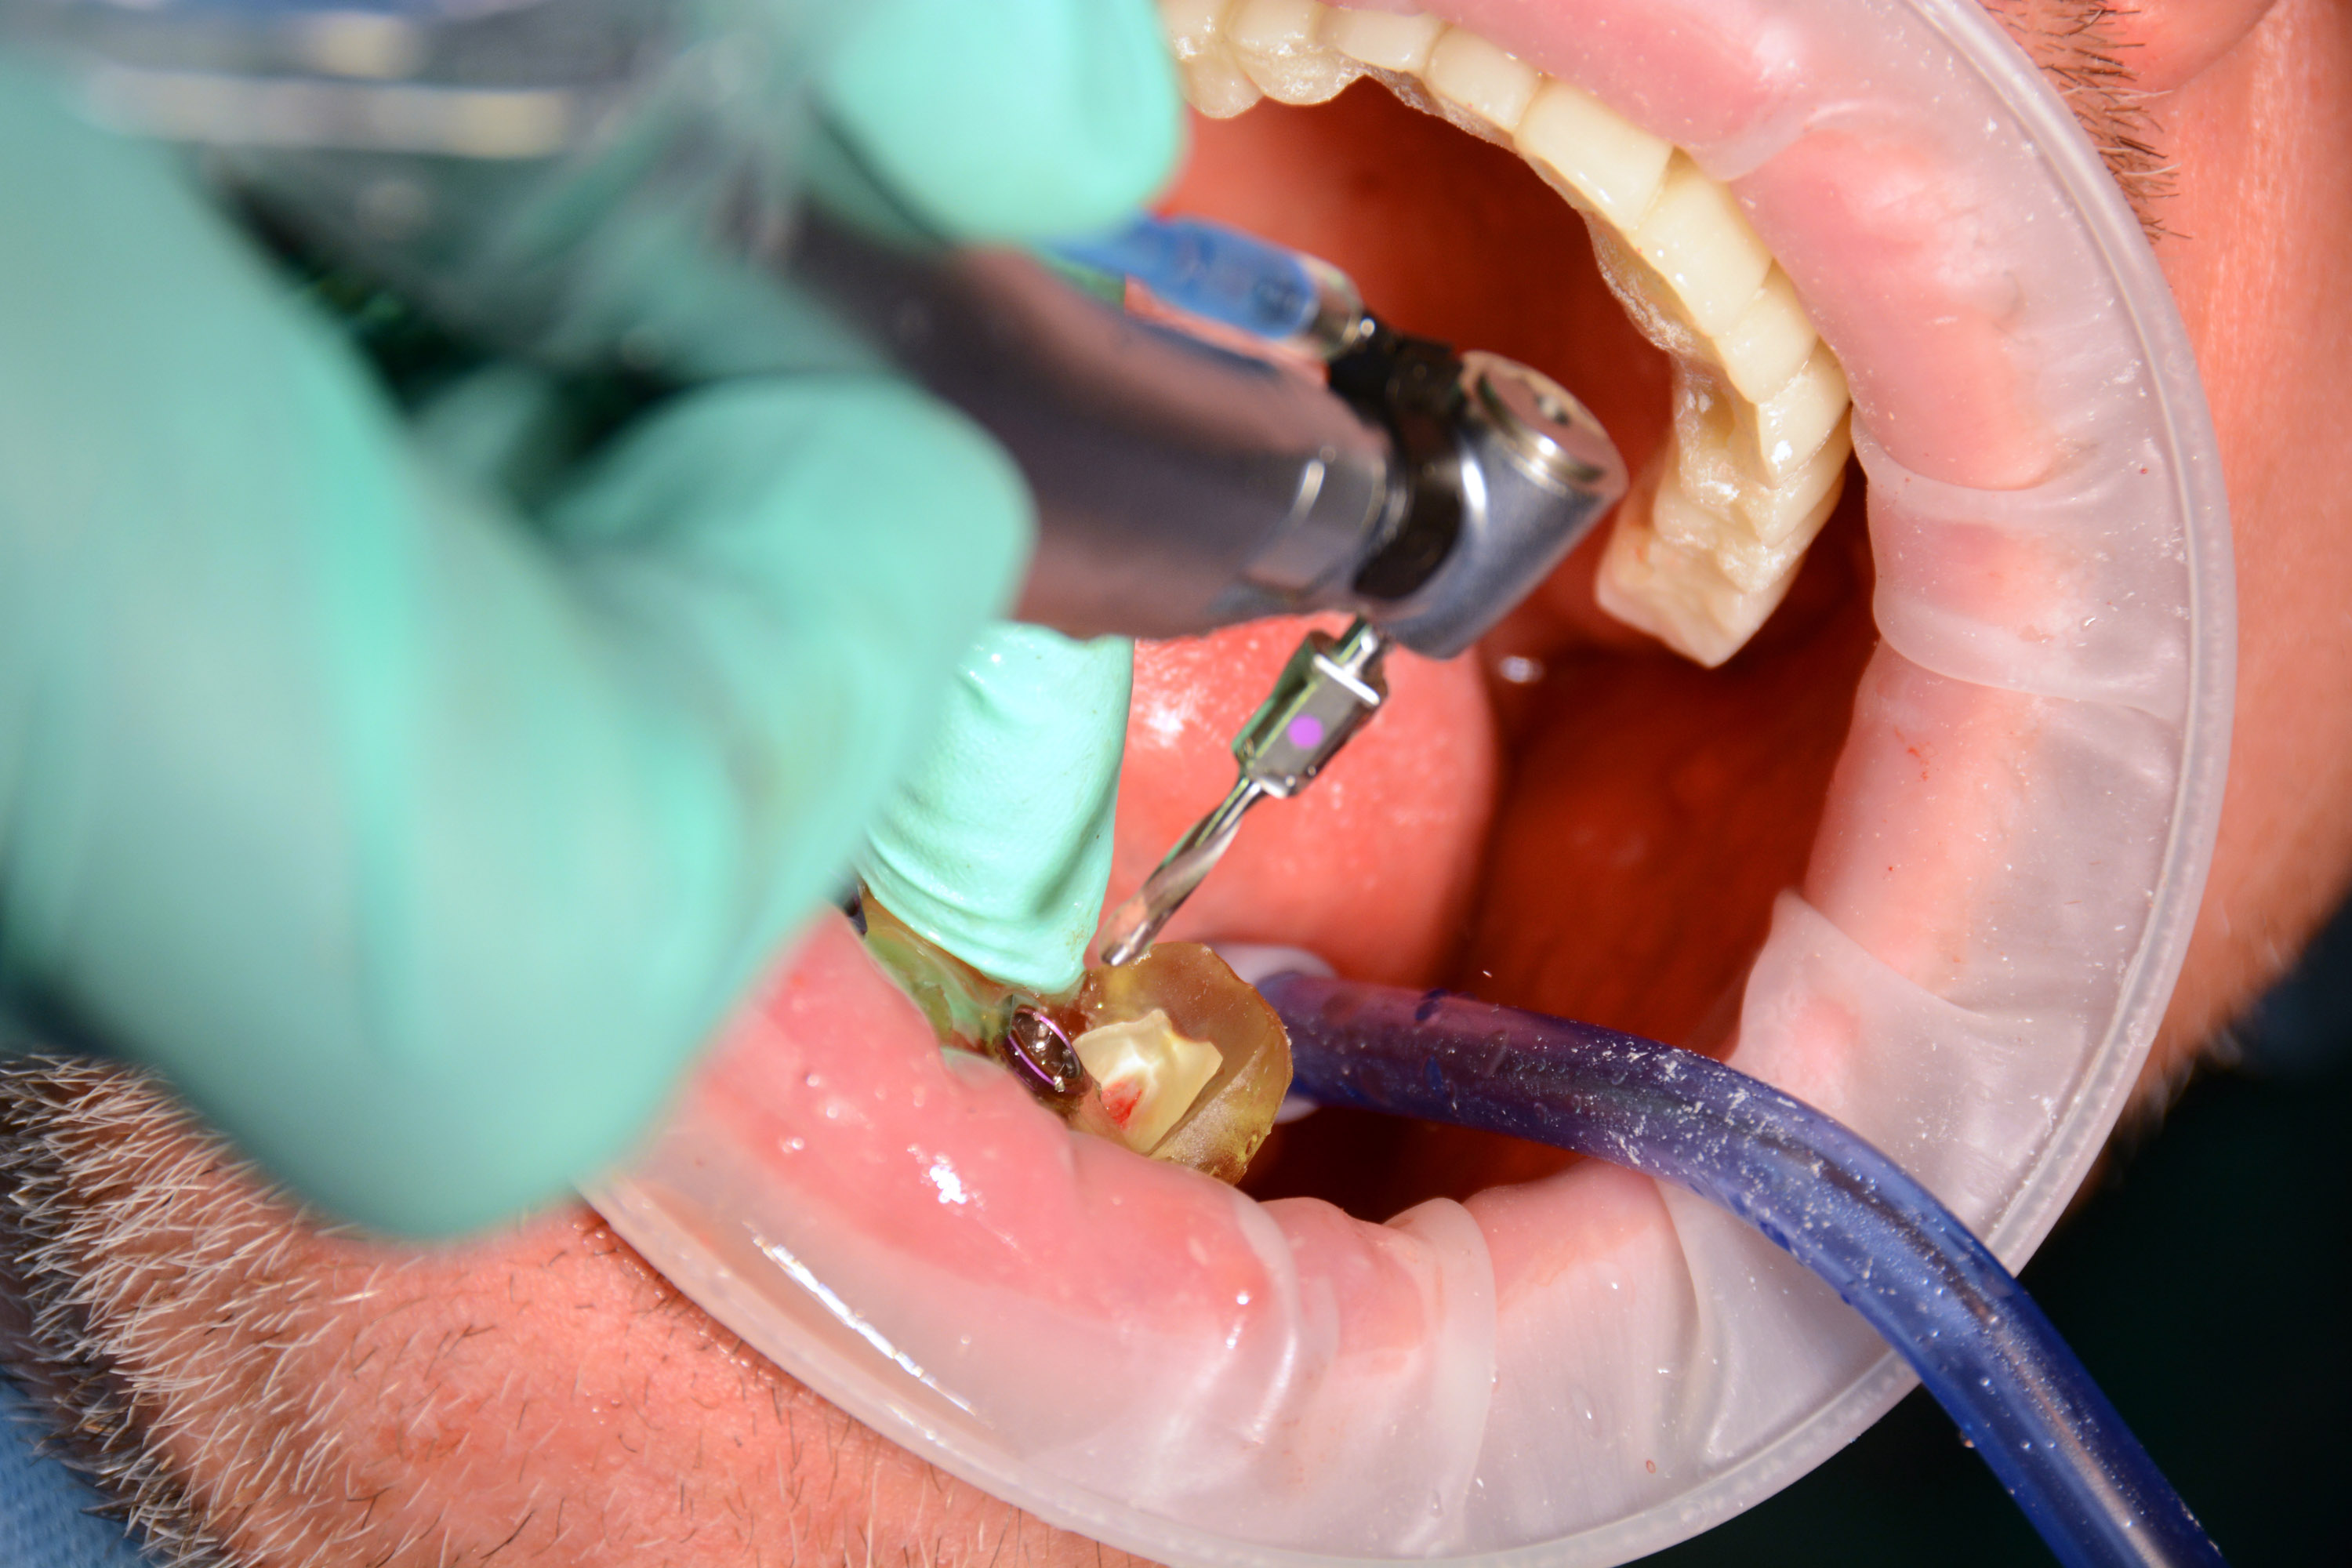

Następnie kursanci pod kierunkiem Dyrektora Naukowego Instytutu Vivadental Dr n. med. Violetty Szycik oraz Mentora Sesji Dr n. med. Adama Nowickiego czynnie uczestniczyli w dwóch złożonych zabiegach z wykorzystaniem pełnej nawigacji chirurgicznej.

Drugi zabieg to pojedyncza implantacja w szczęce z wykorzystaniem szablonu chirurgicznego do pełnej nawigacji.